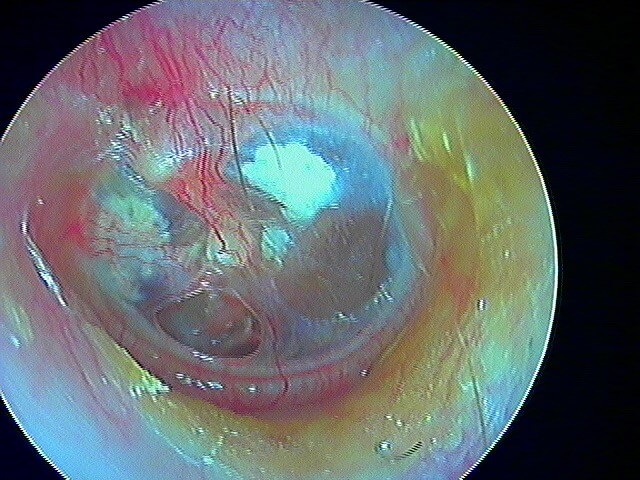

Le/la patient·e avait attendu quelques mois avant de revenir: le cholestéatome a englobé tout le malléus: